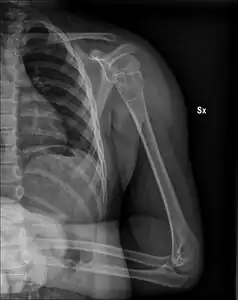

| X-ray: Simple bone cyst in left upper arm of 13 year old | |

Simple bone cysts are often found incidentally on X-rays. About 90 to 95% of the lesion is found in metaphysics of long bones. The cyst is centered, oblong in shape along the long axis of a long bone. Rarely, they are large and multicameral and are found in diaphysis. When fracture is present, there may be a small bone fragment migrated in the cystic fluid. This is called "fallen fragment sign" which is diagnostic of simple bone cyst. Besides, a bubble migrating upwards (known as "rising bubble sign") is another feature suggesting of simple bone cyst.[7]

Unprovoked break in the long bone of the upper arm,, with "fallen leaf" sign. -